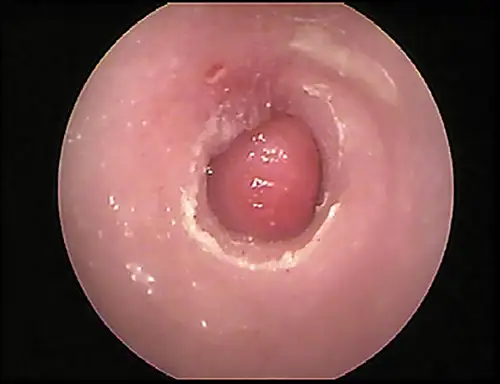

A feline inflammatory polyp originating from the middle ear may also be seen as a fleshy mass protruding into the horizontal canal (Figure 12).

Nasopharyngeal polyp in a cat. A catheter is passed around the fleshy mass and into the tympanic bulla to flush out any mucus or pus in the middle ear prior to polypectomy.

Because the normal pars tensa is translucent, the bulla cavity can be seen when enough light (using a video otoscope) transilluminates the bulla. In otitis media, fluid, if present, can be seen behind the eardrum in the form of bubbles, blood, serum, or pus. Increasing pressure from exudate accumulation can cause the pars tensa to bulge outward. Both of these conditions result in marked pain; pressure must be relieved by myringotomy. Any tissue mass in the middle ear will obscure the ability to view the middle ear (Figure 15). Occasionally, in cats, a middle ear polyp can be seen through the eardrum as a fleshy mass in the bulla.

Otoscopic image of pink mass with red striping seen behind ear drum.

FIGURE 15

Tissue mass behind the eardrum. Note the malleus bone in the pars tensa, indicating the mass is behind the eardrum.